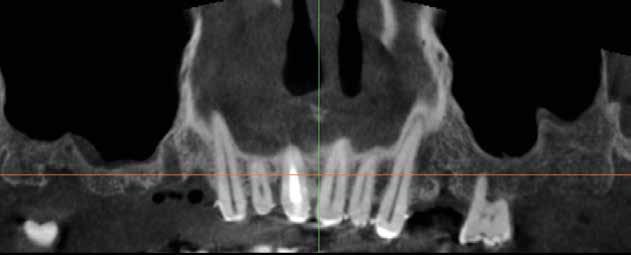

Alla visita di rivalutazione è emerso un ulteriore peggioramento della situazione, confermata anche dall’esame radiografico, con parodontopatia, sanguinamento al sondaggio, infiammazione diffusa, alitosi, difetto parodontale verticale mesiale a 2.3, residui radicolari 1.4, 1.6, 1.7, 3.6, 3.8 e carie destruenti di 1.5, 2.6, 3.5, 3.7 (con lesione endoperio) e 4.7 con estrusione e carie (Figg. 1, 2)

Dopo tre mesi dalla prima fase estrattiva sono stati ripetuti gli esami ematochimici dai quali l’emoglobina glicata del paziente è scesa a 7.2%. Abbiamo pertanto avviato con lo studio pre-implantare che prevede la ceratura diagnostica e gli esami radiologici più avanzati per scegliere i giusti impianti e la loro sede corretta.

L’esame CBCT ha rivelato un quantitativo di osseo sufficiente a procedere con l’intervento implantare, anche se erano ancora visibili le zone delle estrazioni; inoltre ha evidenziato una lesione osteolitica a carico del 3.5 che abbiamo dunque deciso di estrarre (Figg. 7-20).